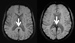

Image: The images show magnetic resonance (MR) slices through the brains of two mountaineers. The image on the left is from a mountaineer who climbed to altitudes above 7,000 meters, and the one on the right is from a mountaineer who survived a high altitude cerebral edema (HACE). The arrows point to the corpus callosum. This part of the corpus callosum is normal in the left image, whereas in the right image (HACE survivor) it shows black spots representing multiple small hemorrhages (microhemorrhages) (Photo courtesy of RSNA/Dr. Knauth et al, University Hospital Gottingen).

The MRI scans revealed brain microhemorrhages almost exclusively in HACE survivors. Of the 10 climbers with a history of HACE, eight had evidence of microhemorrhages on MRI. The other two had uncertain results. Only two of the remaining 26 climbers were positive for microhemorrhages. “It was previously thought that HACE did not leave any traces in the brains of survivors,” Dr. Knauth said. “Our studies show that this is not the case. For several years after, microhemorrhages or microbleeds are visible in the brains of HACE survivors.”

Survivors of the most clinically severe cases of HACE had the most noticeable traces of microhemorrhages on MRI scans. The hemorrhages were found chiefly in the corpus callosum, the thick band of nerve fibers that connects the left and right halves of the brain, and revealed a characteristic distribution different from other vascular diseases such as vasculitis (blood vessel inflammation). “The distribution of microhemorrhages is a new and sensitive MRI sign of HACE and can be detected years after HACE,” Dr. Knauth said. “We will further analyze our clinical and MRI data on patients with acute mountain sickness, which is thought to be a precursor of HACE.”